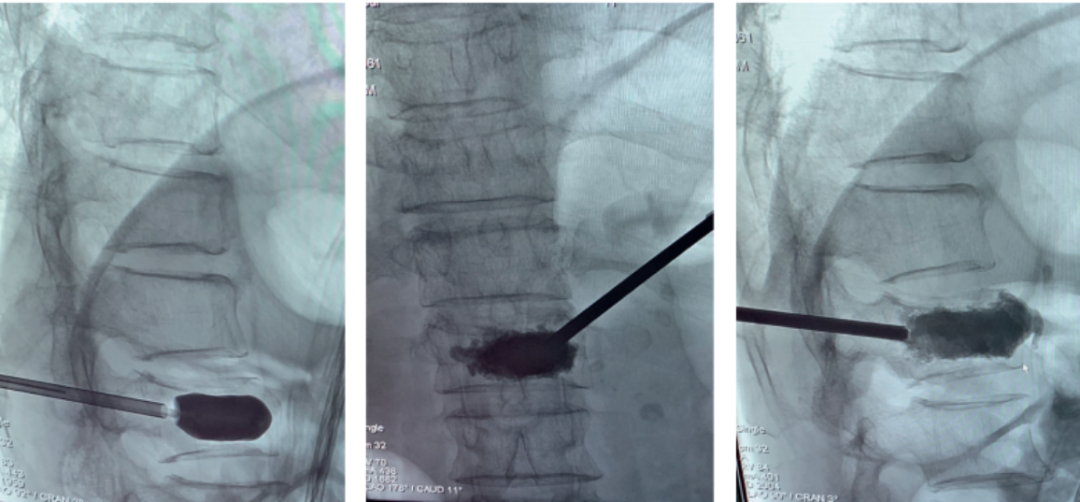

微创手术治疗:包括椎体成形术(PVP)和经皮球囊扩张椎体后凸成形术(PKP),是目前最常用的微创手术治疗方法。通过经皮向骨折椎体注射骨水泥,能够迅速缓解疼痛,增强病椎的强度和刚度,防止椎体进一步塌陷和畸形,而且没有传统开放手术内固定带来的手术创伤以及远期可能出现的内固定失败。PKP还可通过球囊扩张使压缩骨折得到一定程度的复位,球囊取出后在椎体内形成的空腔有利于骨水泥低压力注入,有效降低骨水泥渗漏率。